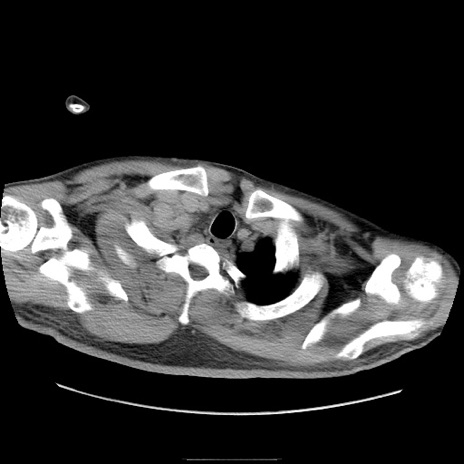

冠状断像